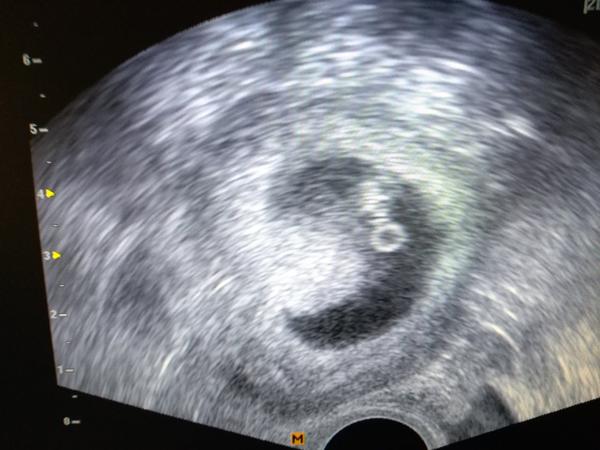

Ahoj,tak dnes kontrolni ultrazvuk...Mudr. Mardesicova byla nadsena,ja zase tolik ne...vypada to tak na 8-10 folikulu,odber v patek.Pane boze,prosim,at to vyjde🙂Uz bychom si to zaslouzili...